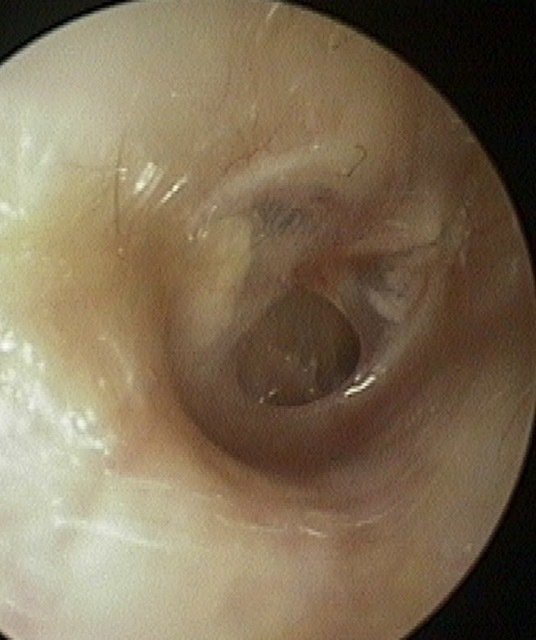

Perforation

Tympanic Membrane